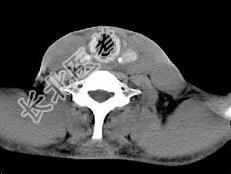

- 单项选择题男,46岁, 外伤后左下颈搏动性肿块,CT如图所示, 最可能的诊断是 ( )

A、左颈部血管瘤

B、左颈动脉体瘤

C、左颈静脉球瘤

D、左颈总动脉假性动脉瘤

E、左颈部动静脉畸形